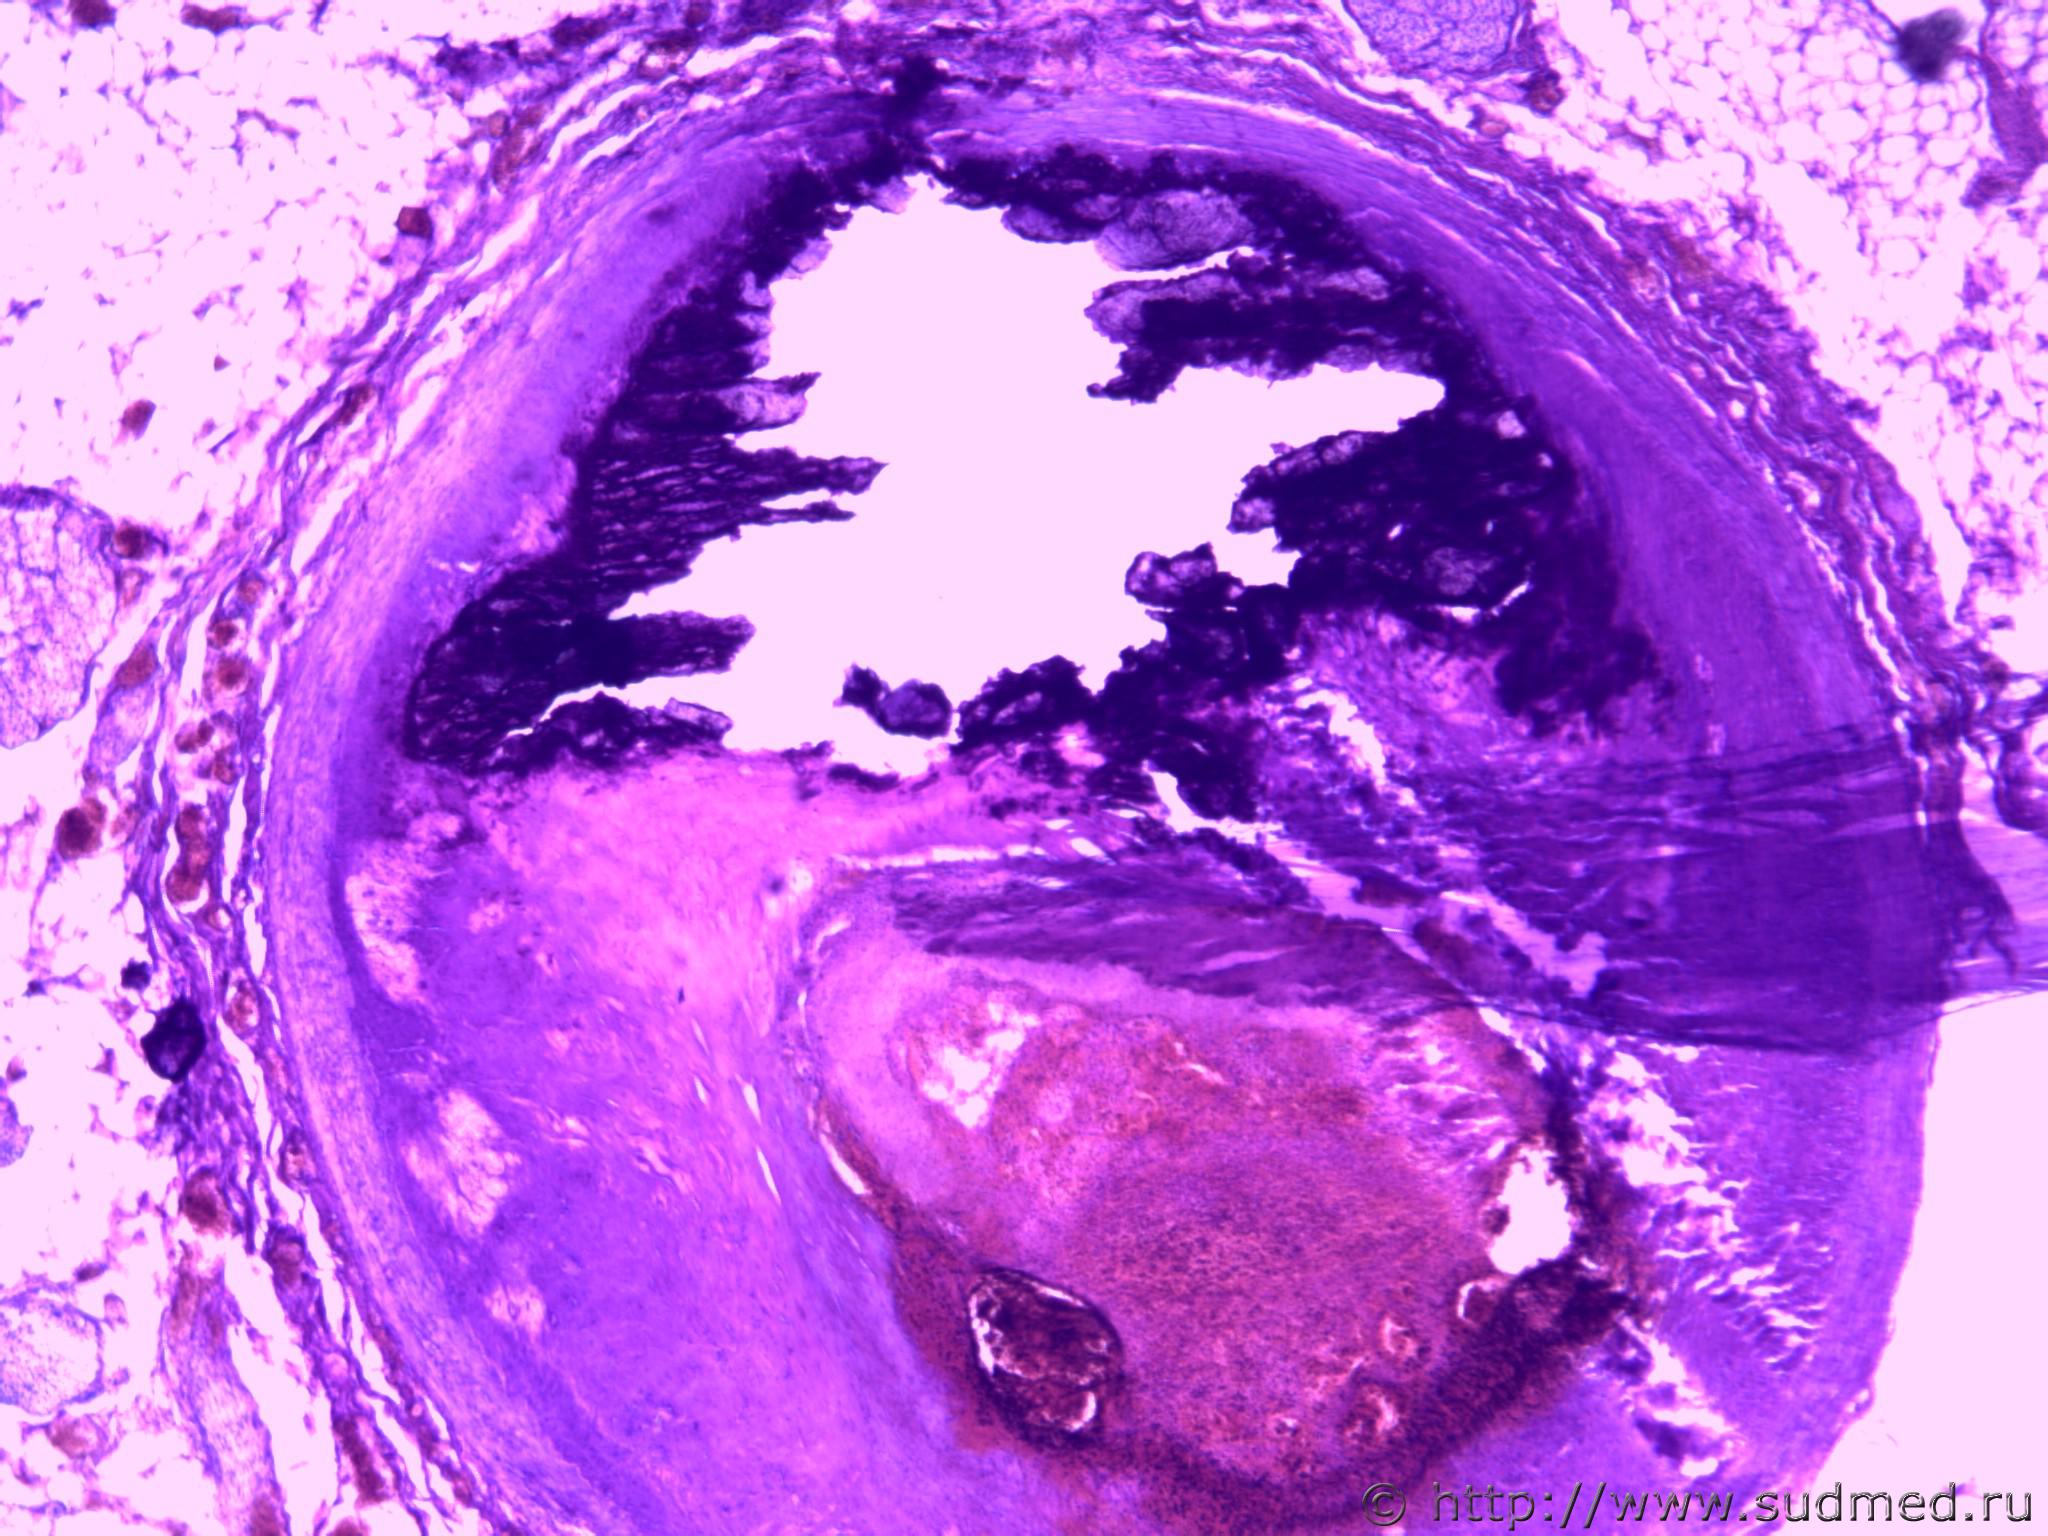

Зрелая тератома яичника (дермоидная киста).

Сообщение отредактировал Chivas - 18.04.2014 - 06:56